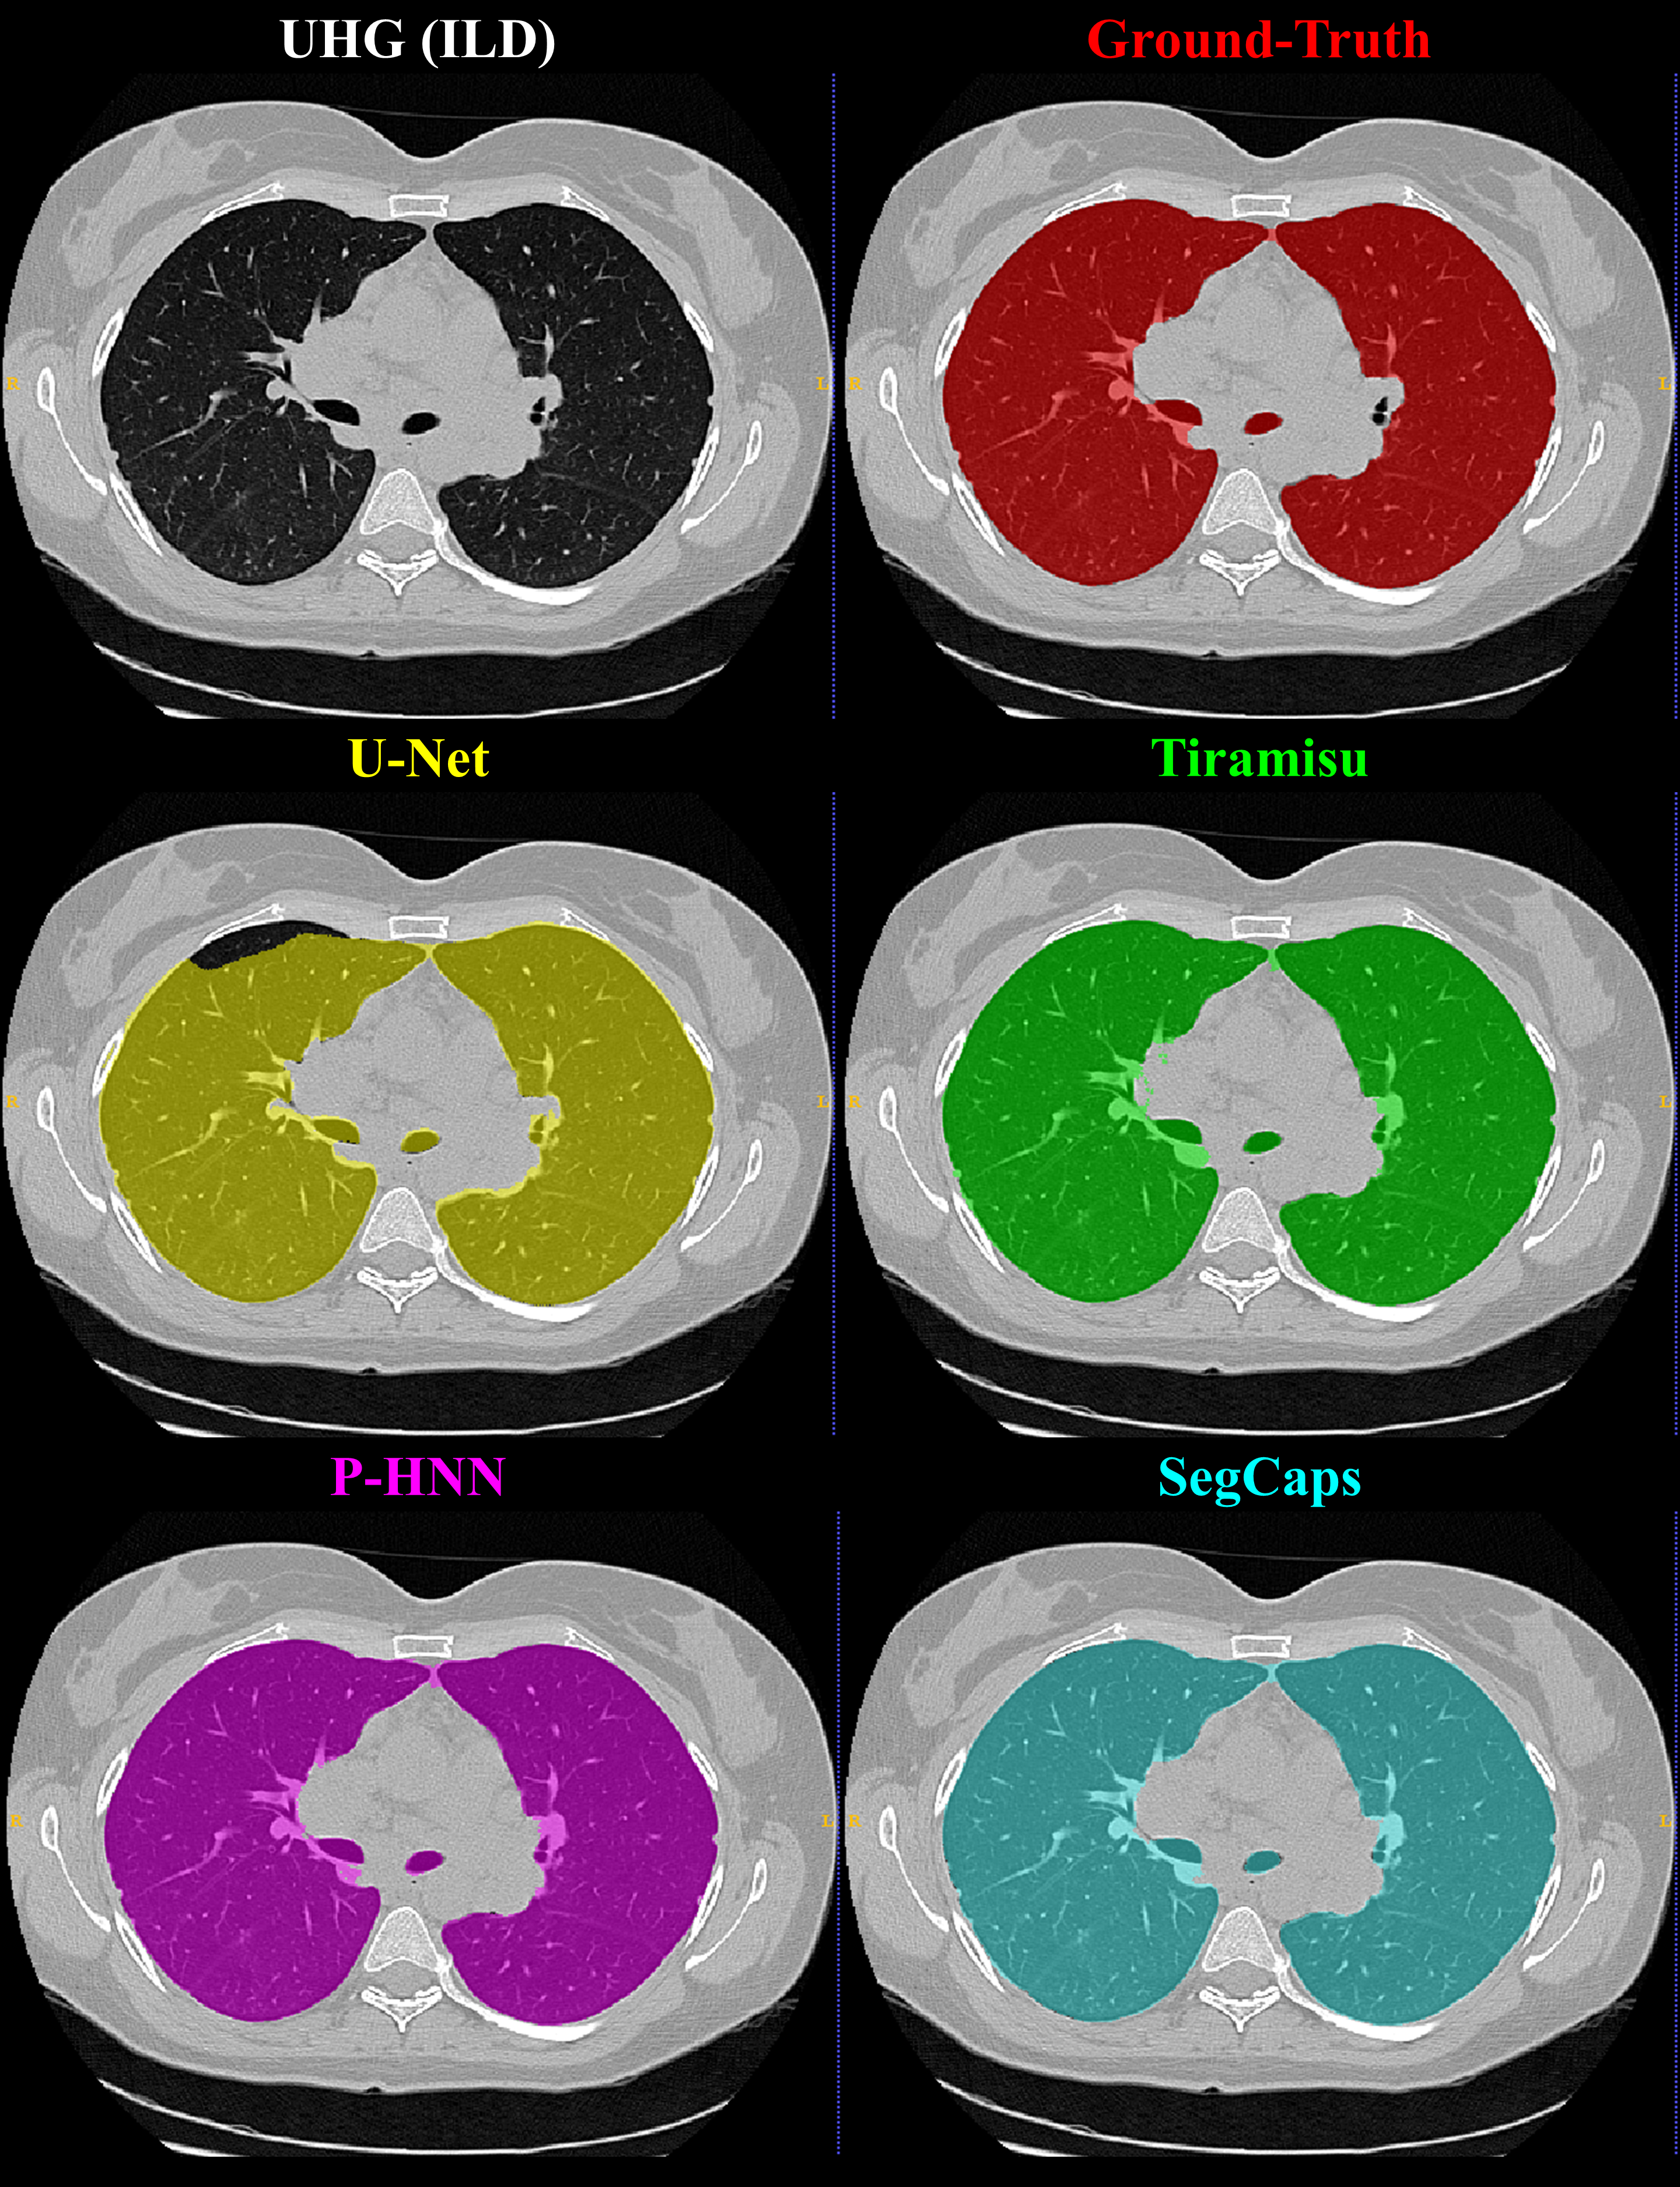

Refer to caption

Fig. 6: Qualitative results for a 2D slice from a CT scan taken from the UHG dataset. It can be noticed that the CNN-based methods’ typical failure cases are where the pixel intensities (Hounsfield units) are far from the class mean (i.e. high values within the lung regions or low values outside the lung regions).

Qualitative results for typical samples from all datasets are shown in Figure s 4 8. As can be seen in these qualitative examples, SegCaps achieves higher results by not falling into the typical segmentation failure causes, namely over-segmentation and segmentation-leakage. These qualitative examples are supported by our quantitative findings where over-segmentation is best captured by the HD metric and segmentation-leakages are best captured by the Dice metric.